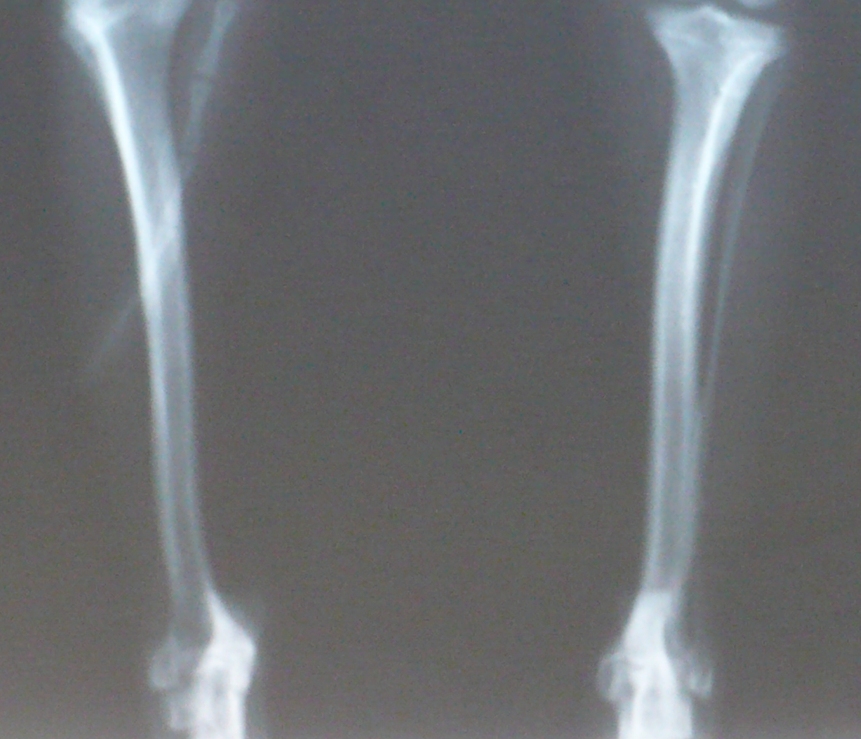

Вот снимок с разным увеличением суставов Микуши. yamagutti, обратите, пожалуйста, внимание и на скакательные суставы, хоть их и мало видно

• 1_1.JPG

Чихуахуа (1.JPG)

169,1 KB · Просмотры: 201

• 1_2.JPG

Чихуахуа (2.JPG)

238,2 KB · Просмотры: 206

• 1_3.JPG

Чихуахуа (3.JPG)

246,3 KB · Просмотры: 208

• 1_4.JPG

Чихуахуа (4.JPG)

299,4 KB · Просмотры: 214